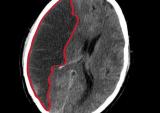

Какую роль играет компьютерная томография при диагностике острого ишемического инсульта. Тема была обсуждена специалистами в ходе дискуссии в МЦ ЭРЕБУНИ. Стартовавшая с февраля 2019г. государственная...